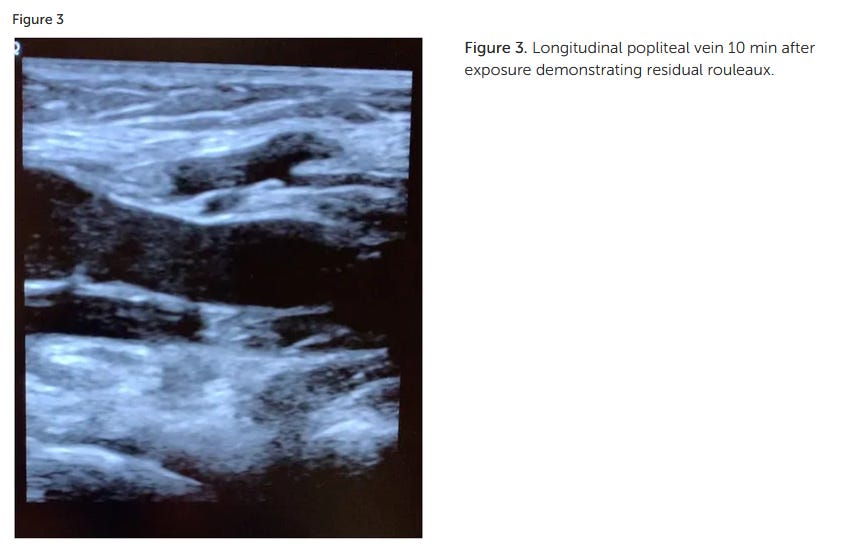

Smart Phone Exposure Shows Rouleaux Formation Via Ultrasound In Large Leg Veins Within Minutes And New Guidelines For Safe Exposure For Kids To Smart Devices - Age 0-6 No Screen Time Is Safe!